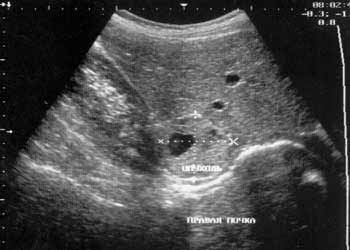

Рис. 5. Опухоль надпочечника с дегенерацией в центре.